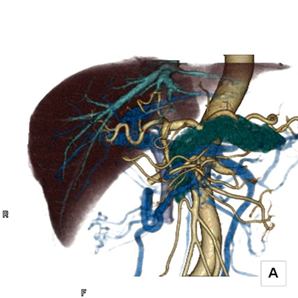

多目的デジタルX線TV装置を用いた胆道系検査・治療、肝腫瘍に対する血管造影検査・治療等を医師、看護師とともにチームで取り組んでいます。

造影検査等の最新技術を用いた精密検査も積極的に行っています。